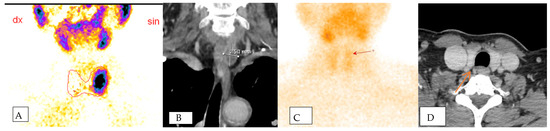

Delving into the SVS results, seven patients showed negative findings. Among these, two did not have clinically proven parathyroid adenomas, while five had false-negative SVS results but were later confirmed to have adenomas intraoperatively. This highlights the dual role of SVS, not only in identifying pathological glands accurately, but also in contributing to the precision of preoperative diagnoses. When SVS correctly lateralized the pathological gland, the PTH gradient was observed to be 1.5–2 times higher than the normal PTH level, providing valuable guidance for localizing the adenoma within the specific anatomical quadrant of the neck (Figure 2).

Figure 2. The figure shows positive scintigraphy (A) and CT scan (B) of the left sided parathadenoma in one patient which localization was confirmed using SVS and postoperative material. Figure (C,D) shows mismatch between two radiological non-invasive methods. Scintigraphy (C) shows suspected left-sided parathadenoma, while CT scan (D) shows right-sided parathadenoma. SVS and operative material confirmed left-sided parathadenoma in this patient.